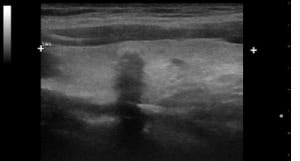

U.a. weisen Gewichtsveränderungen, Zyklusunregelmäßigkeiten und emotionale Instabilität auf Schilddrüsenfunktionsstörungen hin. Derbe Veränderungen in der Schilddrüse hingegen sind verdächtiger als weiche. Zu jeder Schilddrüsenuntersuchung gehört auch der Ultraschall von Schilddrüse und Halsweichteilen (Schilddrüsensonographie). Hierdurch lassen sich Größe und evtl. Veränderungen erkennen sowie relevante Strukturen in der vorderen Halsregion mit beurteilen, insbesondere Nebenschilddrüsen und Lymphknoten. Anhand des Schallmusters und des Durchblutungsmusters (Perfusion) lassen sich häufig bereits Krankheitsbilder festmachen.

So findet sich bei einer Autoimmunhyperthyreose (M. Basedow), einer zumeist schweren Form einer Schilddrüsenüberfunktion, eine ausgeprägte Echoarmut in Verbindung mit einer stark vermehrten Durchblutung des Schilddrüsengewebes. Von den Knoten verdienen solche mit Mikroverkalkungen und einer vermehrten Binnenperfusion verstärkte Aufmerksamkeit.